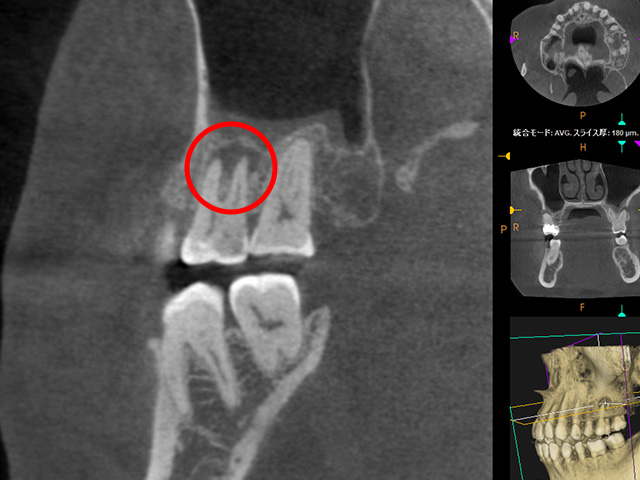

| 検査・診断 | X線(2次元)による診断 | 歯科用CT(3次元)を用いた精密な診断が可能 |

| デンタルレントゲン | CT画像 |